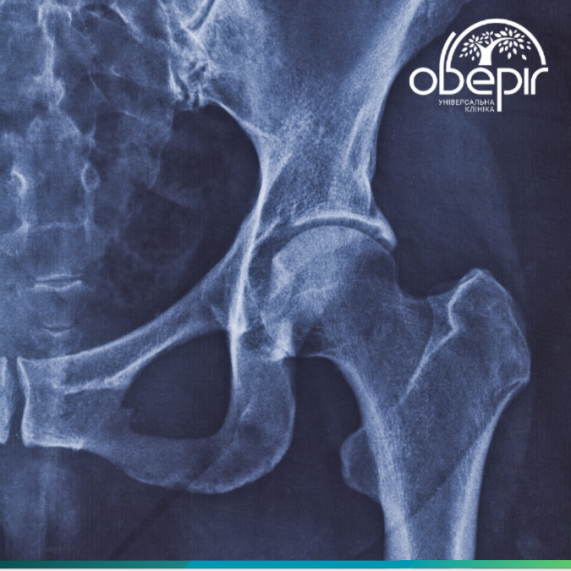

Представьте, что ваш тазобедренный сустав, эта важная «опора», начинает работать не так, как нужно. Вместо плавных движений вы ощущаете боль, скованность, а иногда и характерный «скрип». Если говорить просто, коксартроз — это дегенеративно-дистрофическое заболевание, при котором разрушается хрящ, покрывающий суставные поверхности бедренной кости и тазовой впадины. Со временем это приводит к деформации костей, и сустав теряет подвижность.

Тазобедренный сустав — один из самых крупных в организме. Каждый день он выдерживает огромные нагрузки, позволяя нам ходить, бегать. Его гладкая поверхность обеспечивается суставным хрящом, который действует как амортизатор. При коксартрозе хрящ постепенно истончается, становится шероховатым, а затем исчезает. Без хряща кости начинают тереться друг о друга, вызывая боль, воспаление и образование костных разрастаний. В итоге сустав деформируется и теряет свои функции.

Тяжёлая: боль постоянная, движения резко ограничены, атрофия мышц, хромота, укорочение ноги. На рентгене щель почти отсутствует.

Терминальная: суставная щель отсутствует, хрящ полностью разрушен, кости срастаются (анкилоз), движения невозможны.